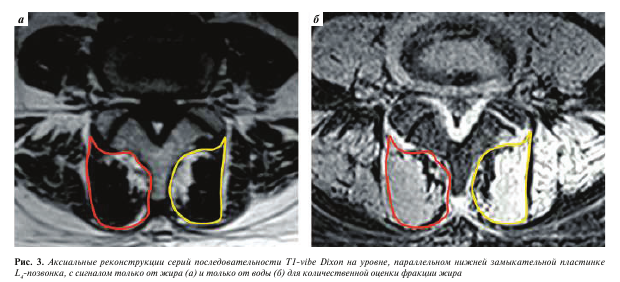

Изображения, полученные с помощью вышеописанной последовательности T1-vibe без жироподавления, открывали в программе InobitecPro в режиме мультипланарной реконструкции, где строились аксиальные срезы, параллельные в коронарной и сагиттальной проекциях нижним замыкательным пластинкам L3-, L4-, Ь5-позвонков (рис. 1). На построенных изображениях на всех 3 уровнях с помощью инструмента «ROI полигон» обводили многораздельные мышцы с обеих сторон, как показано на рис. 2 (вдоль границы остистого и суставного отростков, затем по фасции многораздельной мышцы), для оценки средней интенсивности сигнала и площади выделенной зоны. Кроме того, в режиме T1-vibe без жироподавления с помощью инструмента «ROI овал» измеряли среднюю интенсивность сигнала в жировой клетчатке слева от паравертебральных мышц (см. рис. 2).

У пациентов, которым выполняли режим с методикой жироподавления Dixon, аналогичным образом измеряли интенсивность магнитно-резонансного сигнала на реконструированных сериях с сигналом только от жира (IF) и только от воды (IW) (рис. 3) для расчета показателя фракции жира (fat fraction, FF) по формуле FF = IF/(IW + IF), предложенного изначально для количественной оценки жирового замещения мышц у пациентов с миопатиями [11].